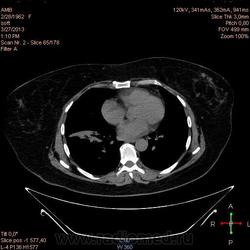

Здравствуйте, коллеги .Нужна помощь.Больная страдает Бронх.астмой.Беспокоять кашель,одышка , слабость, боль левой грудной клетке.Была температура 37,5- 38,0.Данный момент получает цефомизин темпер нормализовалось.Хочеть стационарное леч.Обратите пожалуиста на молочные железы, справа была операция год назад .Беспокоять боль правой мол.железе.

Во-первых, нет дайкомов. По представленным изображениям, изменения в левом легком дифференцировал бы между ТЭЛА мелких ветвей и организующей пневмонией, справа - пока вариантов нет (нужны дайкомы).

+1. Диф. диагностика между ОП и ТЭЛА обоих легких. Исключить ТЭЛА методом КТ с в/в боюсным контрастированием.